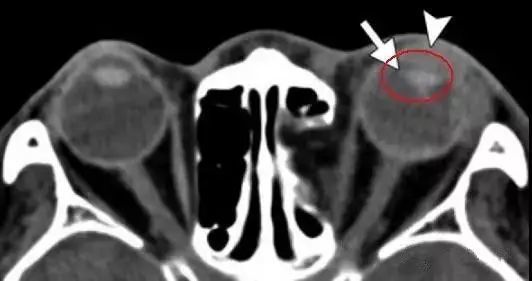

创伤性白内障

对眼球的钝性创伤也可能破坏晶状体囊 , 进而导致晶状体水肿并最终导致白内障的形成 。 白内障在临床检查时比较容易诊断 。

在CT上 , 与未受影响的晶状体相比较 , 受影响的水肿的晶状体可能表现为相对低密度 。 成熟的白内障可能表现为高密度影或含钙化